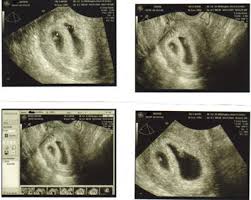

Pregnancy 6 Week Ultrasound Pictures : An Imaging Approach To Early Pregnancy Failure, (a) ultrasound picture showing an enlarged yolk sac at 6 weeks and 1 day of gestation;

Pregnancy 6 Week Ultrasound Pictures : An Imaging Approach To Early Pregnancy Failure, (a) ultrasound picture showing an enlarged yolk sac at 6 weeks and 1 day of gestation;. So the first ultrasound picture can feel momentous: By the sixth week, most expectant mothers know that they are expecting. These are our 6 weeks pregnancy ultrasound pictures 2018. I had a scan at 4 weeks and understandably didn't see anything but a thickened lining? This gives parents the same type of information:

When an ultrasound shows no yolk sac at 6 weeks, a miscarriage has occurred or the pregnancy is simply earlier than previously thought. Ultrasound picture showing an enlarged yolk sac at 8 in pregnancies destined to be lost, different ultrasound markers became abnormal at least one week before the loss. An ultrasound during early pregnancy is usually a transvaginal ultrasound. 6 weeks pregnant belly pictures. By the sixth week, most expectant mothers know that they are expecting.